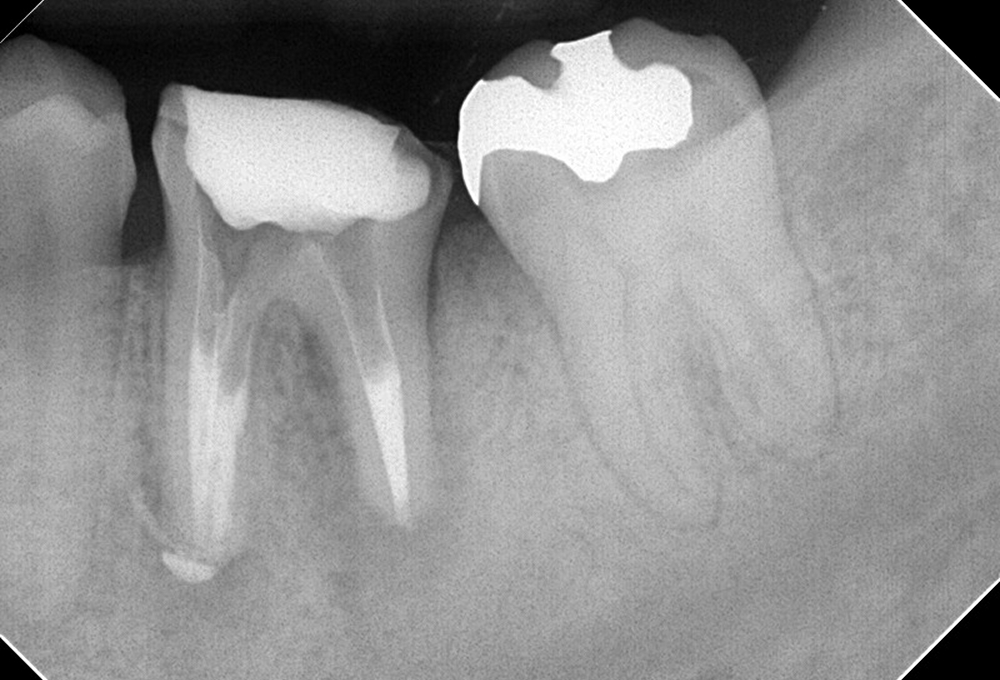

①術前 歯冠大の根尖病変

②術後 感染根管処置後MTAにて根管充填 病変も縮小した